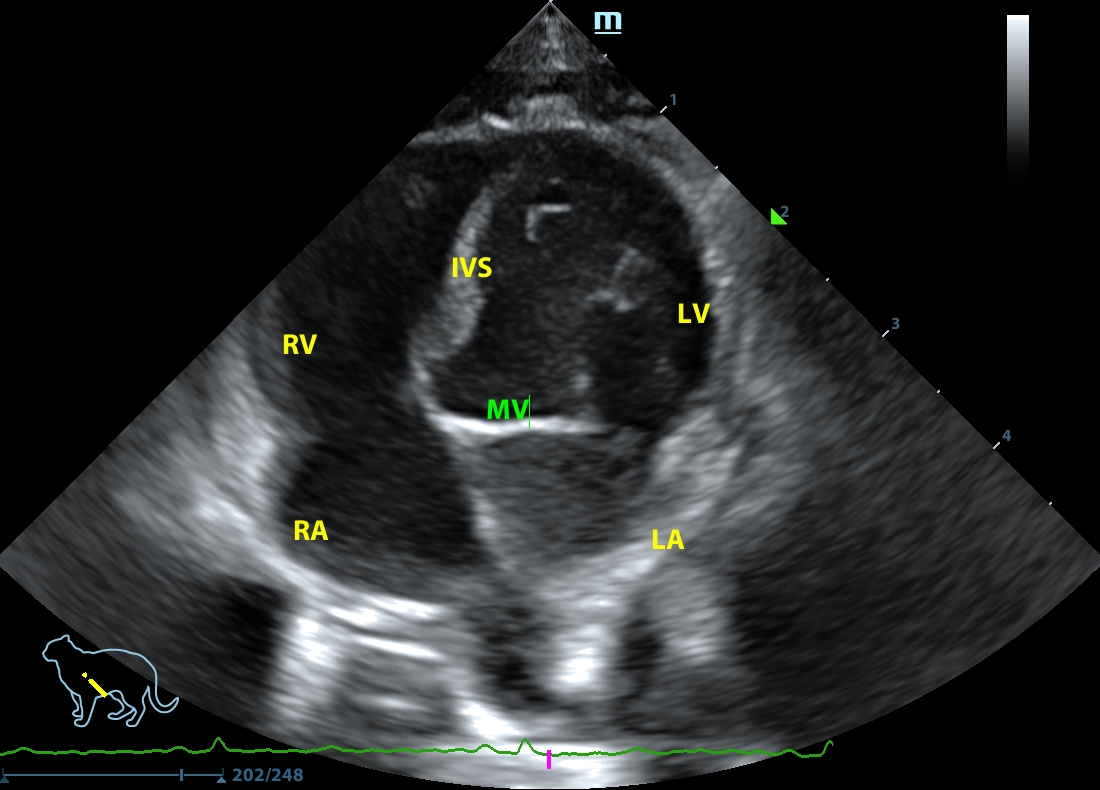

202507112248170159CARD.JPG